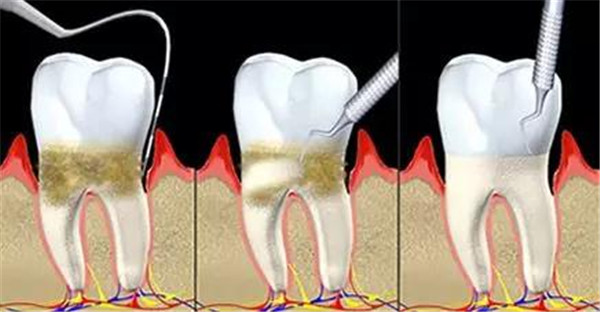

3、龈上洁治术(常规洗牙);

4、龈下刮治术(又称牙周刮治、深层洁牙);

5、牙周手术治疗:包括牙龈切除术和牙龈成形术、翻瓣术、植骨术